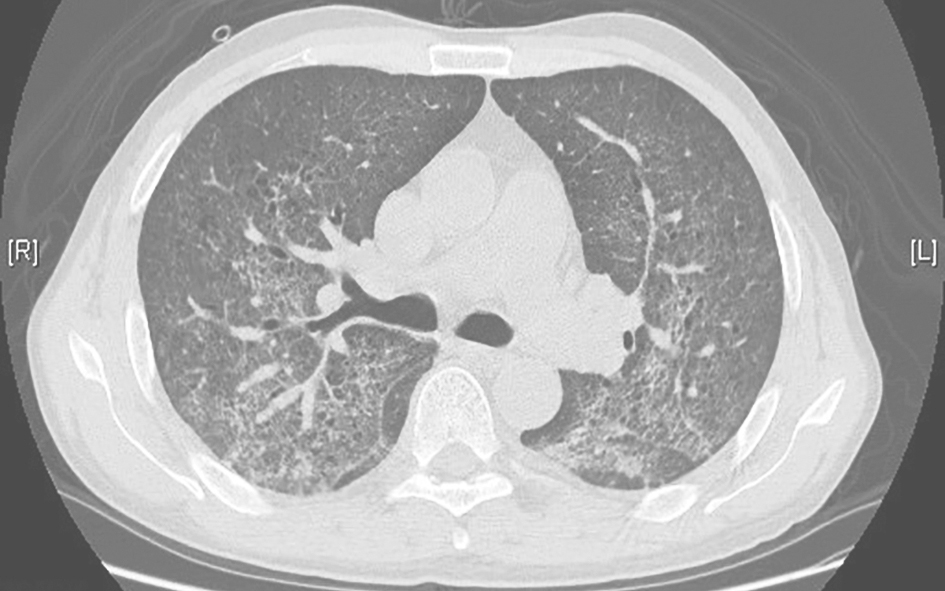

图2结缔组织疾病并发间质性肺炎胸部CT表现

胸部CT可见双肺弥漫性间质性病变,伴肺内斑片高密度影,小叶间隔增厚

图3尘肺合并右侧气胸胸部CT表现

胸部CT可见双肺中上肺为主的高密度实变影,肺内结节影伴小叶间隔增厚,间隔旁肺气肿,右侧少量气胸,双侧胸膜肥厚

图4急性心力衰竭肺水肿胸部CT表现

胸部CT可见双肺弥漫性磨玻璃样、实变高密度伴双侧少量胸腔积液